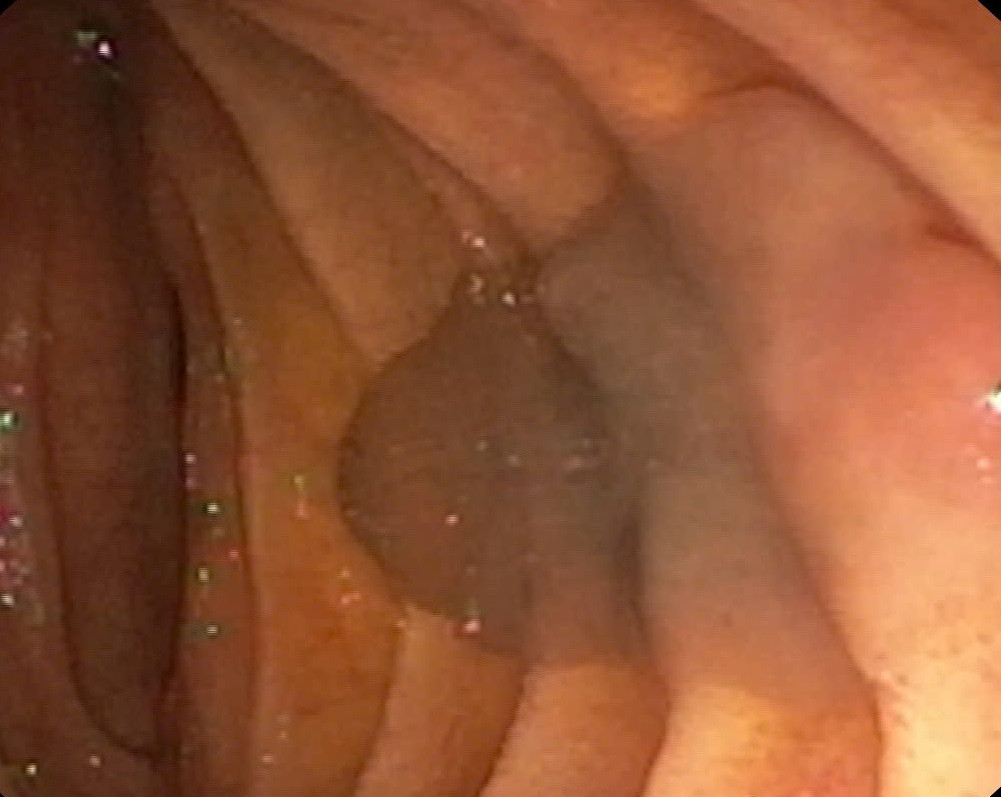

| Sán lá gan được phát hiện trên hình ảnh camera nội soi |

BS Nguyễn Đình Tùng cho biết: “Trong quá trình nội soi mật tụy ngược dòng, quan sát dưới màn hình C-Arm nhận thấy ống mật chủ của bệnh nhân giãn khoảng 10mm, đoạn cuối có bóng nhỏ không ngấm thuốc. Sau đó, các bác sĩ tiến hành cắt nhú vater, dùng bóng kéo ra được con sán lá gan kích thước khoảng 20mm ra khỏi cơ thể người bệnh. Mẫu sán được xét nghiệm định danh là sán lá gan lớn”.